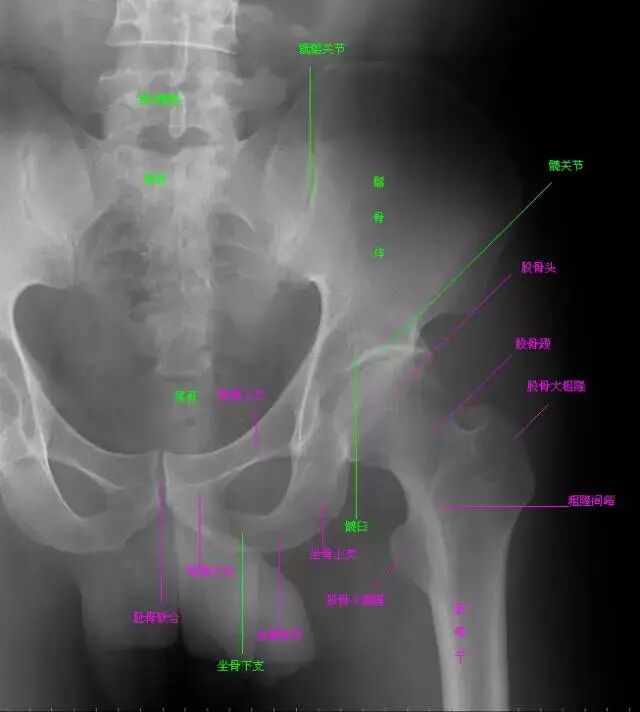

△ 图1 骨盆正位片

在X线像上,构成髋骨的三个部分融合于髋臼,可清晰分辨。髂骨翼的内侧1/4影像与骶骨影像重叠,外侧3/4因有髂窝而较透亮。髂嵴阴影较致密,边缘不光滑,外侧可见髂前上棘影,髂后上棘则重叠于骶骨影内。

弓状线及骨盆腔内侧壁形成复合影像,外侧可见弧形的髋臼阴影。髋臼阴影的上段粗而致密,中段较细,它向下绕过髋臼切迹前部的下缘,与耻骨体的内面形成一条“U”形的致密线,称为泪滴线(Koekler泪滴),泪滴线二脚之间的距离,即髋臼窝的厚度。

髋臼内下方的透亮影为闭孔。闭孔影的上界是耻骨上支、外侧界是坐骨体的下份,坐骨结节阴影与其重叠。坐骨棘的阴影呈三角形突向盆腔。

骨盆前后位片上,骶骨中线应通过耻骨联合。骶髂关节左右对称,关节间隙下半部分可以显示,上半部常投影出模糊双线影。界线的影像在女性呈卵圆形,在男性略呈鸡心形。髂嵴连线影正好通过第4、5腰椎间隙。

由髂嵴影向外可追踪到骼前上、下棘,由髂前下棘到股骨颈外上缘的连线称髂颈线,用以判定髋关节是否正常。正位片上,可以测量耻骨下角,男性为锐角,女性为钝角。

女性骨盆径线的测量,可以采用正位(见图1)和侧位。正位片上,界线影像最远点连线为入口横径,正常为12.3 cm;两侧坐骨棘连线为中骨盆横径,正常为10.5 cm;两侧坐骨结节间距为小骨盆出口横径,正常为11.8 cm。

正位线片上,因髋臼三骨之间以“Y”形软骨相连,融合之前,表现为横行带状透亮影,其宽窄随着年龄变化而改变。年龄越小此透亮带越宽;年龄越大,透亮带变窄,15~17岁左右消失。

股骨头大部套在髋臼内,表面光滑,为致密的细弧线。头的中心偏后下部有一小凹陷,是股骨头凹,有时可投影到股骨头弧线内侧,显示为小环形透亮圈。